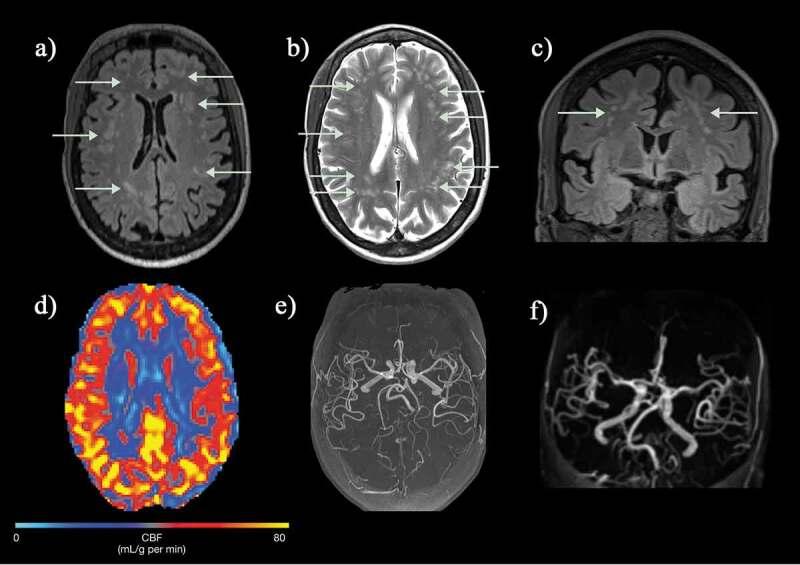

: Over the past decades, neuroimaging studies have clarified that a significant proportion of patients with sickle cell disease (SCD) have functionally significant brain abnormalities. Clinically, structural magnetic resonance imaging (MRI) sequences (T2, FLAIR, diffusion-weighted imaging) have been used by radiologists to diagnose chronic and acute cerebral infarction (both overt and clinically silent), while magnetic resonance angiography and venography have been used to diagnose arteriopathy and venous thrombosis. In research settings, imaging scientists are increasingly applying quantitative techniques to shine further light on underlying mechanisms.: From a June 2020 PubMed search of 'magnetic' or 'MRI' and 'sickle' over the previous 5 years, we selected manuscripts on T1-based morphometric analysis, diffusion tensor imaging, arterial spin labeling, T2-oximetry, quantitative susceptibility, and connectivity.: Quantitative MRI techniques are identifying structural and hemodynamic biomarkers associated with risk of neurological and neurocognitive complications. A growing body of evidence suggests that these biomarkers are sensitive to change with treatments, such as blood transfusion and hydroxyurea, indicating that they may hold promise as endpoints in future randomized clinical trials of novel approaches including hemoglobin F upregulation, reduction of polymerization, and gene therapy. With further validation, such techniques may eventually also improve neurological and neurocognitive risk stratification in this vulnerable population.

在过去的几十年中,神经影像学研究已经阐明,相当一部分镰状细胞病(SCD)患者存在功能上显著的大脑异常。临床上,放射科医生使用结构磁共振成像(MRI)序列(T2、FLAIR、弥散加权成像)来诊断慢性和急性脑梗死(显性和临床无症状),而磁共振血管造影和静脉造影则用于诊断血管病变和静脉血栓形成。在研究环境中,成像科学家越来越多地应用定量技术来进一步揭示潜在的机制。